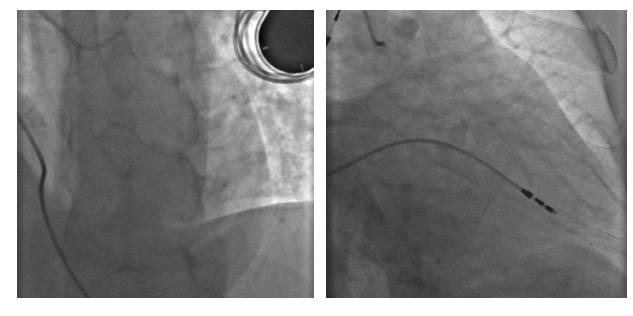

2016-12-4PCI术后植入临时起搏器

冠脉造影结果

冠脉造影结果(右冠)

ECMO(急性心肌梗死 心源性休克)2016-12-4